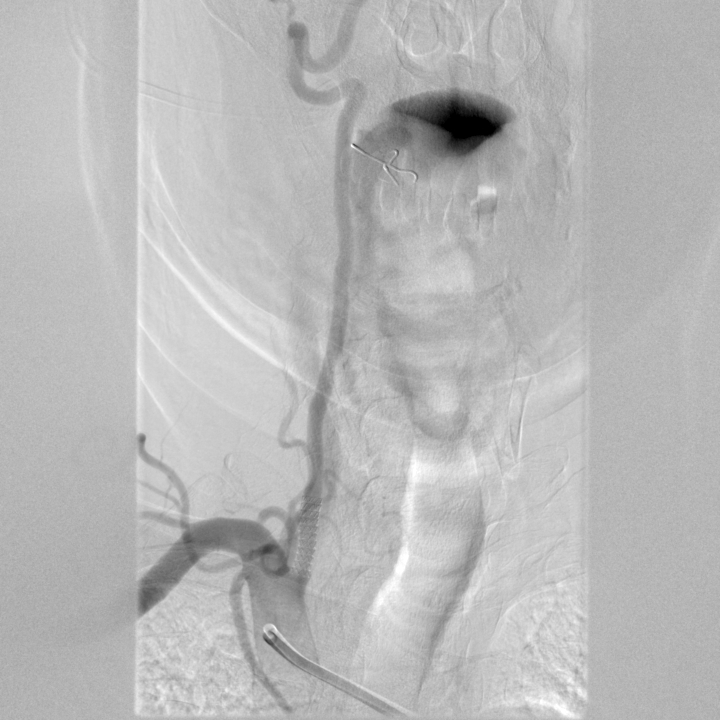

門靜脈高壓治療

tips手術(shù)治療前

tips手術(shù)治療后